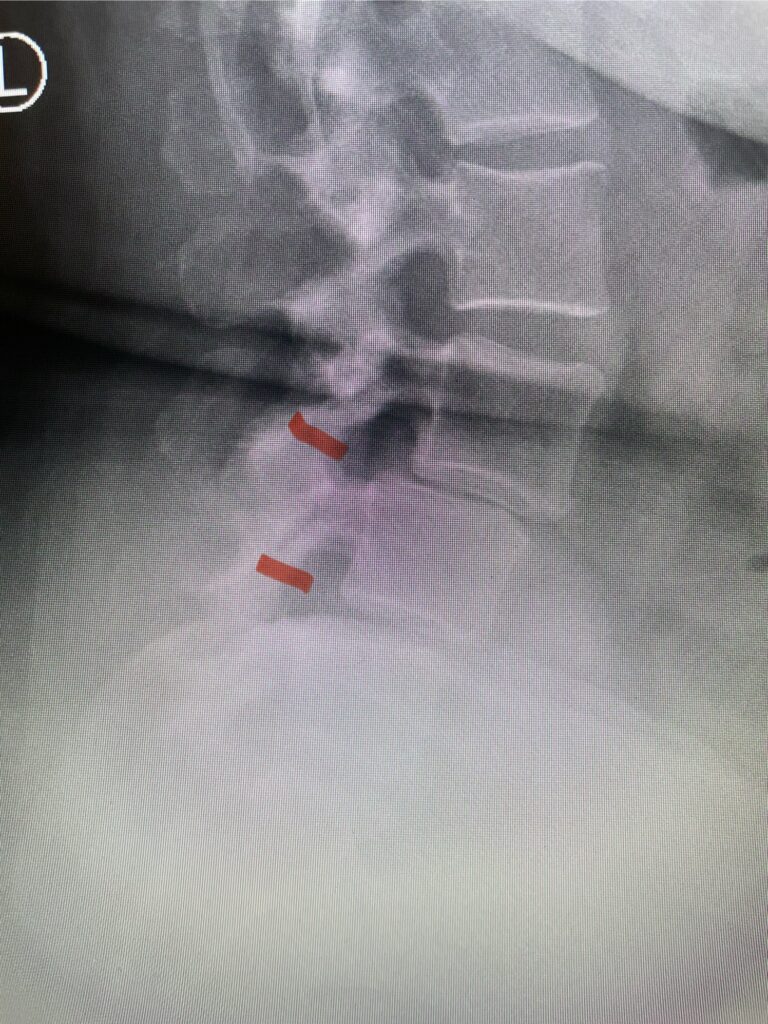

Patients may require an occipital-cervical fusion for both cranio-cervical and atlanto-axial instability, depending on the anatomy. Patients who have long segment posterior cervical fusions can sometimes […]

Here is a tough case: This is a 72 year-old male who presented with several months of progressive neck pain without symptoms of the arms or legs. […]